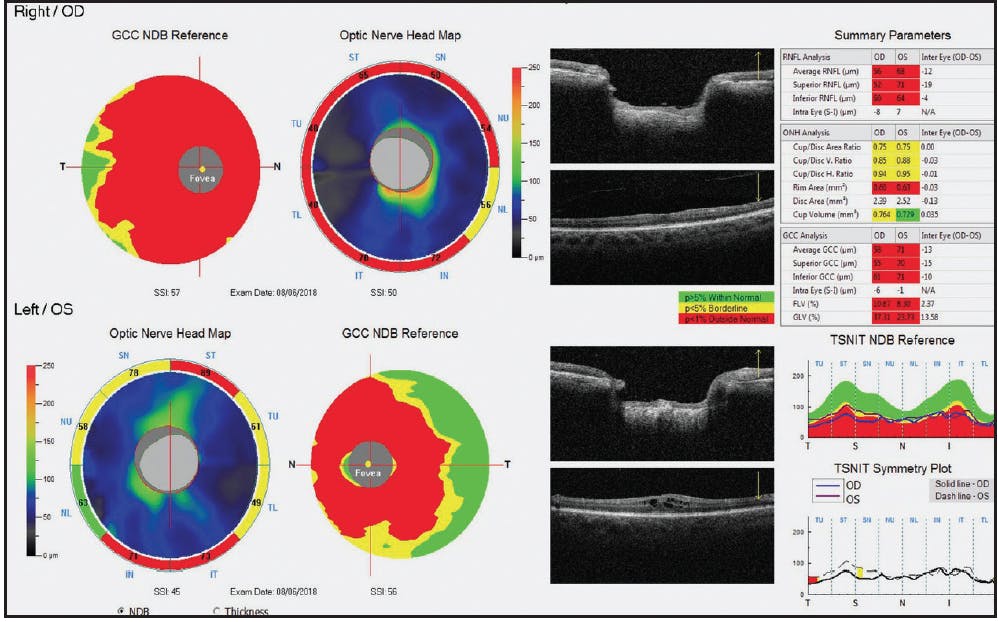

Gonioscopy was open to scleral spur OU with a few areas of pinpoint peripheral anterior synechiae inferiorly in the right eye; of note, the tube entered the eye just anterior to the TM in the right eye. VF and OCT showed advanced loss in both eyes (Figures 4 and 5).

Figure 5. OCT optic nerve head maps and ganglion cell complex thickness maps showed advanced retinal nerve fiber layer and ganglion cell complex damage in both eyes.